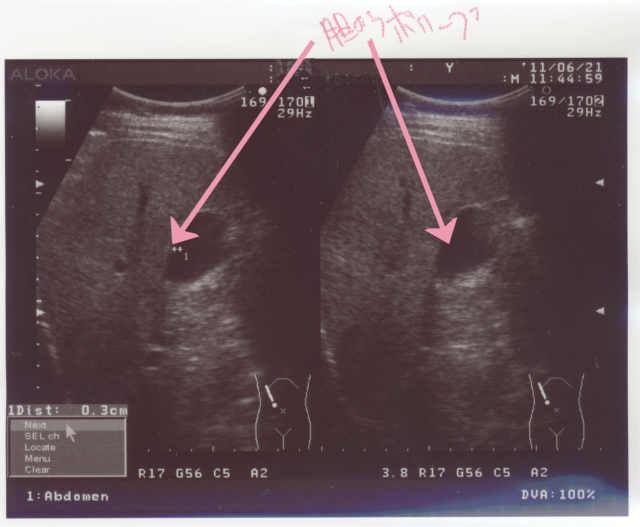

続いて胆のう。

Tannou

3年前にも言われた、胆のうのポリープ。

2~3mmの大きさ。

これも、脂肪だから問題ないってさ。catface